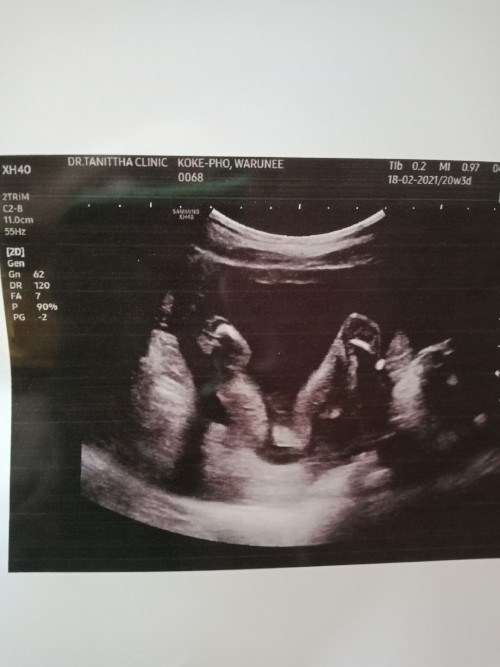

หนูชื่อมะลิค่ะ ยกขาโชว์เลย